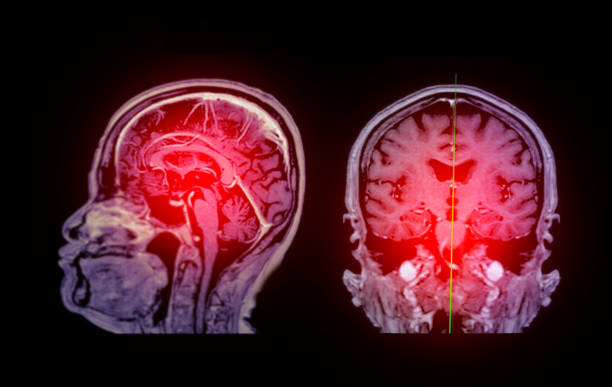

缺血性腦卒中,又稱腦梗死,是一種因腦部血液循環(huán)障礙導(dǎo)致的腦組織壞死疾病。它給患者帶來(lái)的不僅是身體上的痛苦,更是心理上的巨大壓力。